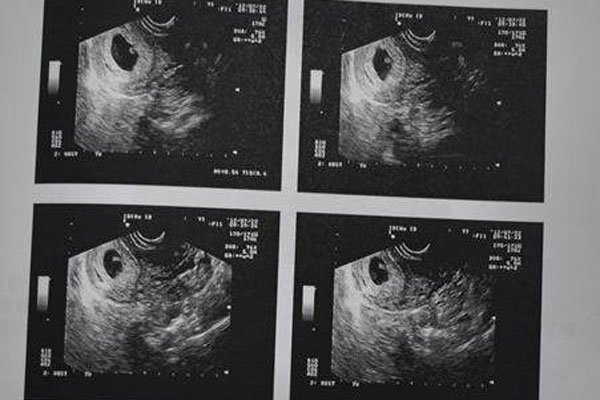

但是如果孕妇出血一直都是鲜红色的,那么一定要注意了,会发生这种情况一般是因为怀孕初期胚胎着床不稳定,出现这种情况并不代表是流产,只能说流产的几率比较大。第二种可能性是宫外孕,孕妇在6-7周时,用超声波还未看到胚胎,但是却有出血的症状,并且人类绒毛膜激素偏高时,这很可能就是宫外孕的情况,孕妈妈要注意伴随出血的同时是否有下腹疼痛的情况发生,有的话要立即就医。

最后一种情况是胎盘早期剥离,这种情况可能发生在孕期的任何一个阶段,一般情况下胎盘早期剥离是没有特殊征兆的,可能会有一些腹痛和急性出血的情况,也可能出现没有胎动,胎儿心率下降等,最好的办法就是去医院作进一步的检查,至于十男九漏这种说法还是不要相信了,本身怀了孕就比较辛苦,各个方面都需要多加小心注意,因此大家还是要更科学的看待这件事情,不然酿成大祸后悔也来不及。